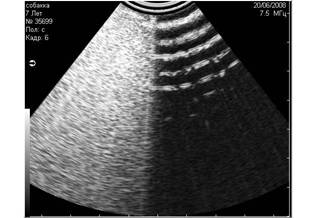

2. Дистальное затухание

При сканировании глубоко расположенных структур, получение качественного изображения затрудняется. Это связано с тем, что на глубоко расположенные структуры у ультразвукового луча остаётся мало энергии(4).

Рис. 6. Дистальное затухание. На снимке этот артефакт представлен тёмной полосой в дистальной части скана. Часто этот артефакт имитирует жидкостные структуры. |